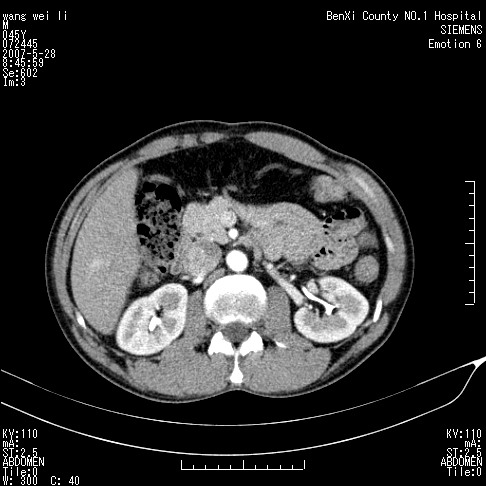

以下是引用还珠格格在2007-5-28 12:06:00的发言:[br]肝右叶后段病灶动脉期结节状强化,既然静脉期、延迟期为等密度充填 应考虑 肝右叶后段典型血管瘤。